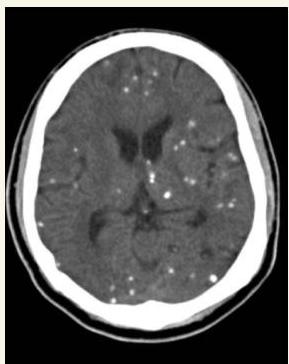

Congenital Toxoplasmosis

This child was delivered with jaundice, HSM, wide spread rashes and progressive head enlarging. Mather gave history of contact with cats early in her pregnancy.

- Diagnosis?

- Congenital Toxoplasmosis “Lipic Vaginal” (Lipic Vaginal), - differential - CMV if paraventricular

CT Finding: Intracranial calcification (extensive cerebral calcifications) — scattered pattern.

- CNS calcifications (tram calcification pattern)

- Calcification in the border called “tram calcification”

- CMV has calcification around the ventricles (C-shape)